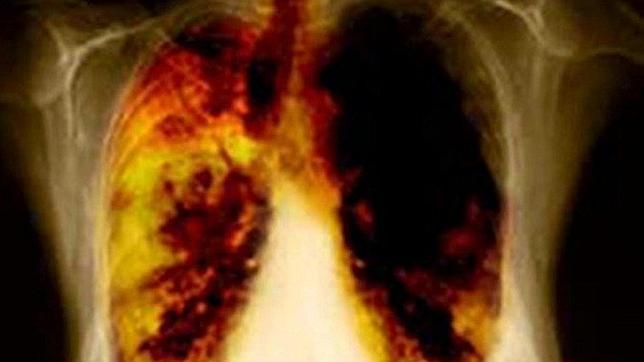

Descubren una terapia para prevenir el crecimiento del cáncer de pulmón

Según reseña la revista, el cáncer de pulmón es una de los más agresivos y se ha convertido en una de las causas más comunes de muertes por cáncer en el mundo. Y a pesar de los avances en la biología molecular aún no se conoce completamente a los mecanismos que utilizan las células cancerígenas para crecer y diseminarse por todo el cuerpo.